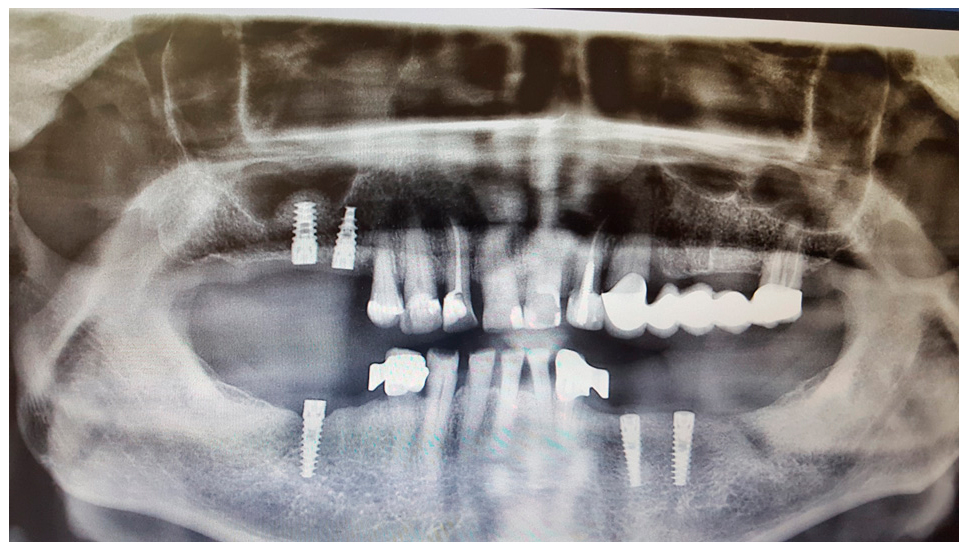

Sinus lifting was performed simultaneously with implantation. (Syntoss Bone Graft, DSI Premium Implants, DSI Silk 5.0 sutures). After a four-month recovery period, trepan open implants and abutments added using a direct impression technique.

A week after, the new smile was there.